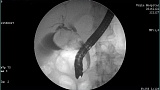

- Атлас